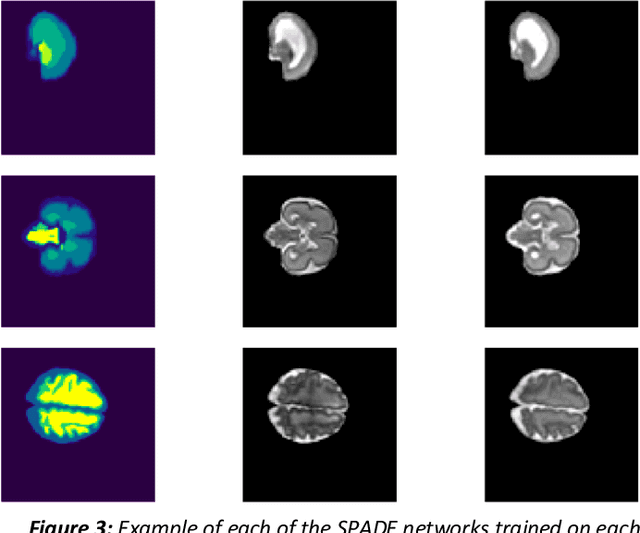

Abstract:Fetal brain magnetic resonance imaging serves as an emerging modality for prenatal counseling and diagnosis in disorders affecting the brain. Machine learning based segmentation plays an important role in the quantification of brain development. However, a limiting factor is the lack of sufficiently large, labeled training data. Our study explored the application of SPADE, a conditional general adversarial network (cGAN), which learns the mapping from the label to the image space. The input to the network was super-resolution T2-weighted cerebral MRI data of 120 fetuses (gestational age range: 20-35 weeks, normal and pathological), which were annotated for 7 different tissue categories. SPADE networks were trained on 256*256 2D slices of the reconstructed volumes (image and label pairs) in each orthogonal orientation. To combine the generated volumes from each orientation into one image, a simple mean of the outputs of the three networks was taken. Based on the label maps only, we synthesized highly realistic images. However, some finer details, like small vessels were not synthesized. A structural similarity index (SSIM) of 0.972+-0.016 and correlation coefficient of 0.974+-0.008 were achieved. To demonstrate the capacity of the cGAN to create new anatomical variants, we artificially dilated the ventricles in the segmentation map and created synthetic MRI of different degrees of fetal hydrocephalus. cGANs, such as the SPADE algorithm, allow the generation of hypothetically unseen scenarios and anatomical configurations in the label space, which data in turn can be utilized for training various machine learning algorithms. In the future, this algorithm would be used for generating large, synthetic datasets representing fetal brain development. These datasets would potentially improve the performance of currently available segmentation networks.